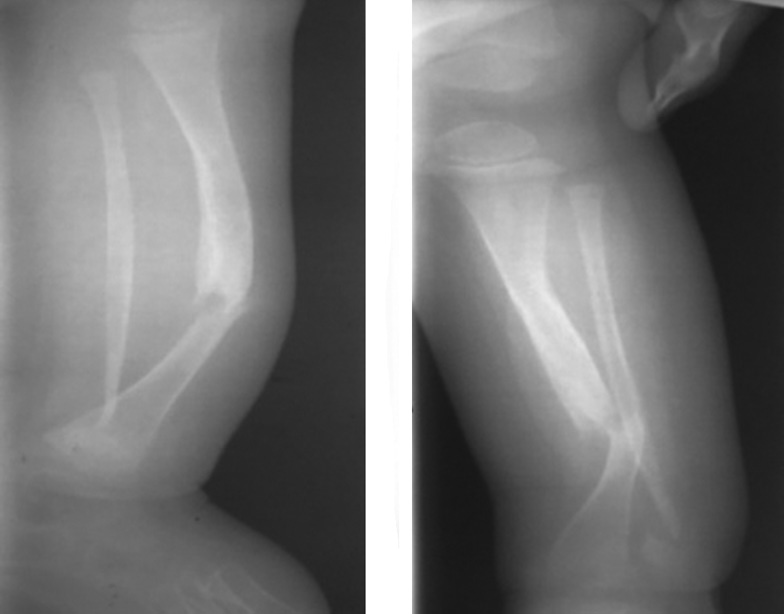

- Impaired support ability of the limb (Fig 3).

Fig. 3. X-ray imaging of the right tibia bones in two views before microsurgical autografting